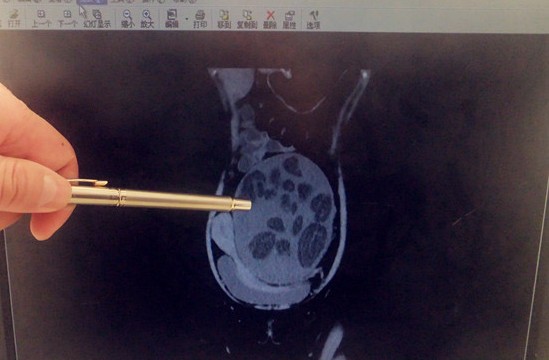

房燕的腹腔明顯被畸胎瘤填滿

????11月29日消息房燕(化名)是一位年僅25歲的單身女性,但前段時(shí)間她的腹部卻像孕婦般一天天隆起,讓人匪夷所思。經(jīng)青島市立醫(yī)院婦科確診,房燕患了巨大腹膜后畸胎瘤。10月11日市立醫(yī)院婦科為房燕成功實(shí)施了腫瘤切除手術(shù),切除的腫瘤相當(dāng)于一個(gè)兒童用足球大小。

????“女孩來的時(shí)候,就像是挺著一個(gè)懷孕6個(gè)月的肚子?!笔辛⑨t(yī)院婦科主任陳龍觀看了房燕重新做的B超、MR和CT,初步判斷腫瘤為良性畸胎瘤。了解到房燕對(duì)將來婚姻生活的渴求和美好愿景,陳龍決定為房燕采取微創(chuàng)腔鏡手術(shù)。但陳龍表示,此次微創(chuàng)手術(shù)難度很大,根據(jù)目前國(guó)內(nèi)文獻(xiàn)上所記錄的,此類情況均是進(jìn)行開腹手術(shù),否則承擔(dān)的風(fēng)險(xiǎn)較大。

????“畸胎瘤一般與遺傳有關(guān),99%都長(zhǎng)在卵巢。由于目前的影像檢查都無法直接看到房燕體內(nèi)腫瘤生長(zhǎng)的準(zhǔn)確位置,所以只有微創(chuàng)手術(shù)真正開始后,才發(fā)現(xiàn)房燕的這個(gè)腫瘤竟然長(zhǎng)在腹膜后,這就比較罕見了。在全國(guó)像發(fā)現(xiàn)這么大的腹膜后腫瘤都沒有過報(bào)道,而且又是使用腹腔鏡進(jìn)行治療,這就要求手術(shù)高度精準(zhǔn)?!标慅堈f。

????陳龍介紹,整臺(tái)微創(chuàng)手術(shù)進(jìn)行了2個(gè)多小時(shí),主要是為了避免感染,需要先用負(fù)壓吸引管將腔內(nèi)腫瘤內(nèi)的油脂性物質(zhì)吸出,再將腫瘤與各臟器進(jìn)行剝離,保證不破壞周圍血管及神經(jīng),尤其是腫瘤上達(dá)臍上兩橫指,兩側(cè)達(dá)側(cè)盆壁,下達(dá)盆底,與病人的尾骨緊密相連,要謹(jǐn)慎確保病人術(shù)后肢體能正?;顒?dòng),最后才能將腫瘤殘壁徹底取出。